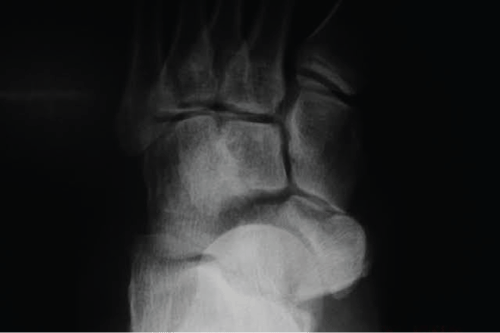

Patient of 39-years-old, female, business woman of the transport branch, was admitted to the emergency room, after suffering a truck fall, reporting that she was wearing high heels at the time of the fall. She presented a sprain in her left foot with severe edema. Normal neurovascular physical examination. An X-ray performed, which showed isolated dislocation of the navicular and rupture of the dorsal talonavicular, calcaneonavicular and cuneonavicular ligaments (Figure 1). No lesion on the posterior tibial tendon reported. According to the AO and Tscherne classification of closed fractures, it was a closed fracture grade 0 (Fr. C 0) [7].

Figure 1: Preoperative X-ray showing isolated dislocation of the tarsal navicular.